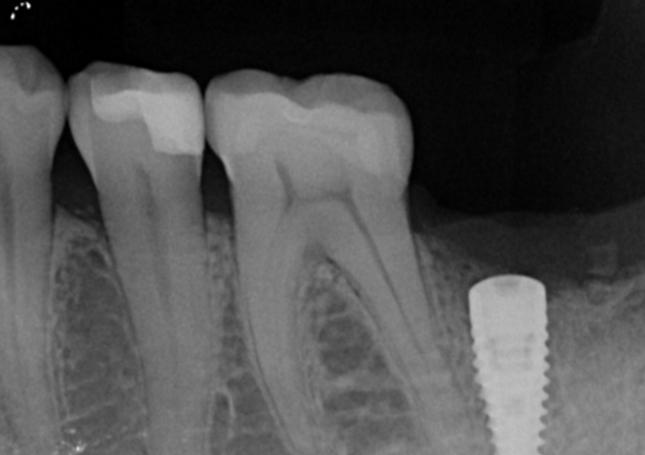

Tooth #47 underwent root canal treatment at another clinic a decade ago.

Two weeks prior to the current visit, the ceramic crown, along with its post and core, became dislodged, leaving the residual tooth structure compromised.

Pre-extraction images